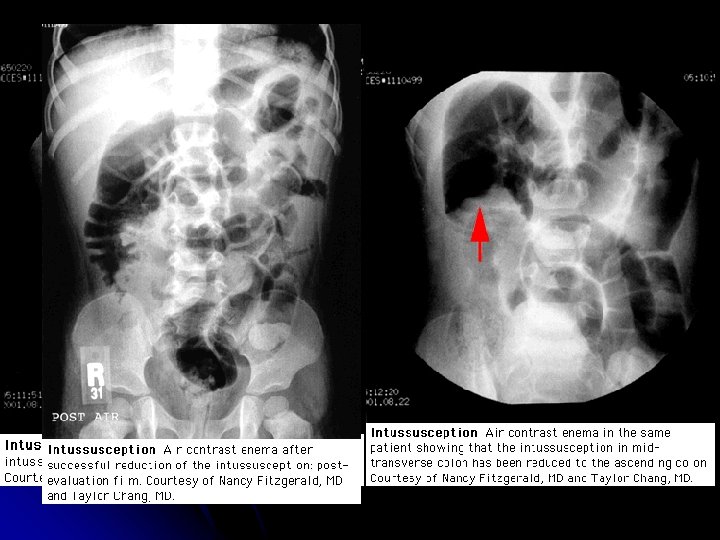

Diagnosis & Treatment l (3 -2) Contrast studies: l The standard procedure for diagnosis and treatment of intussusception is a contrast (air or radiopaque) enema. l Barium and water-soluble contrast l Air contrast l Nonoperative reduction using barium or air contrast techniques is successful in approximately in 75 to 90 percent of patients with ileo-colic intussusception.